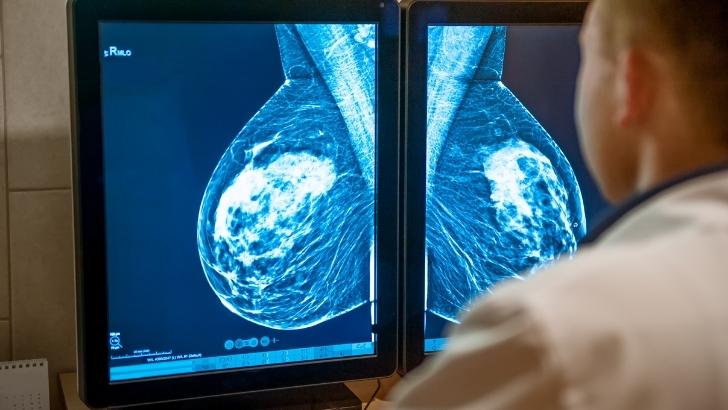

- Mamografi: Meme kanseri taramalarında en yaygın kullanılan yöntemdir. Mamografi, meme dokusunun röntgen görüntülerini çeker ve anormal kitleler, kireçlenmeler veya lezyonlar tespit edilmesine yardımcı olur.